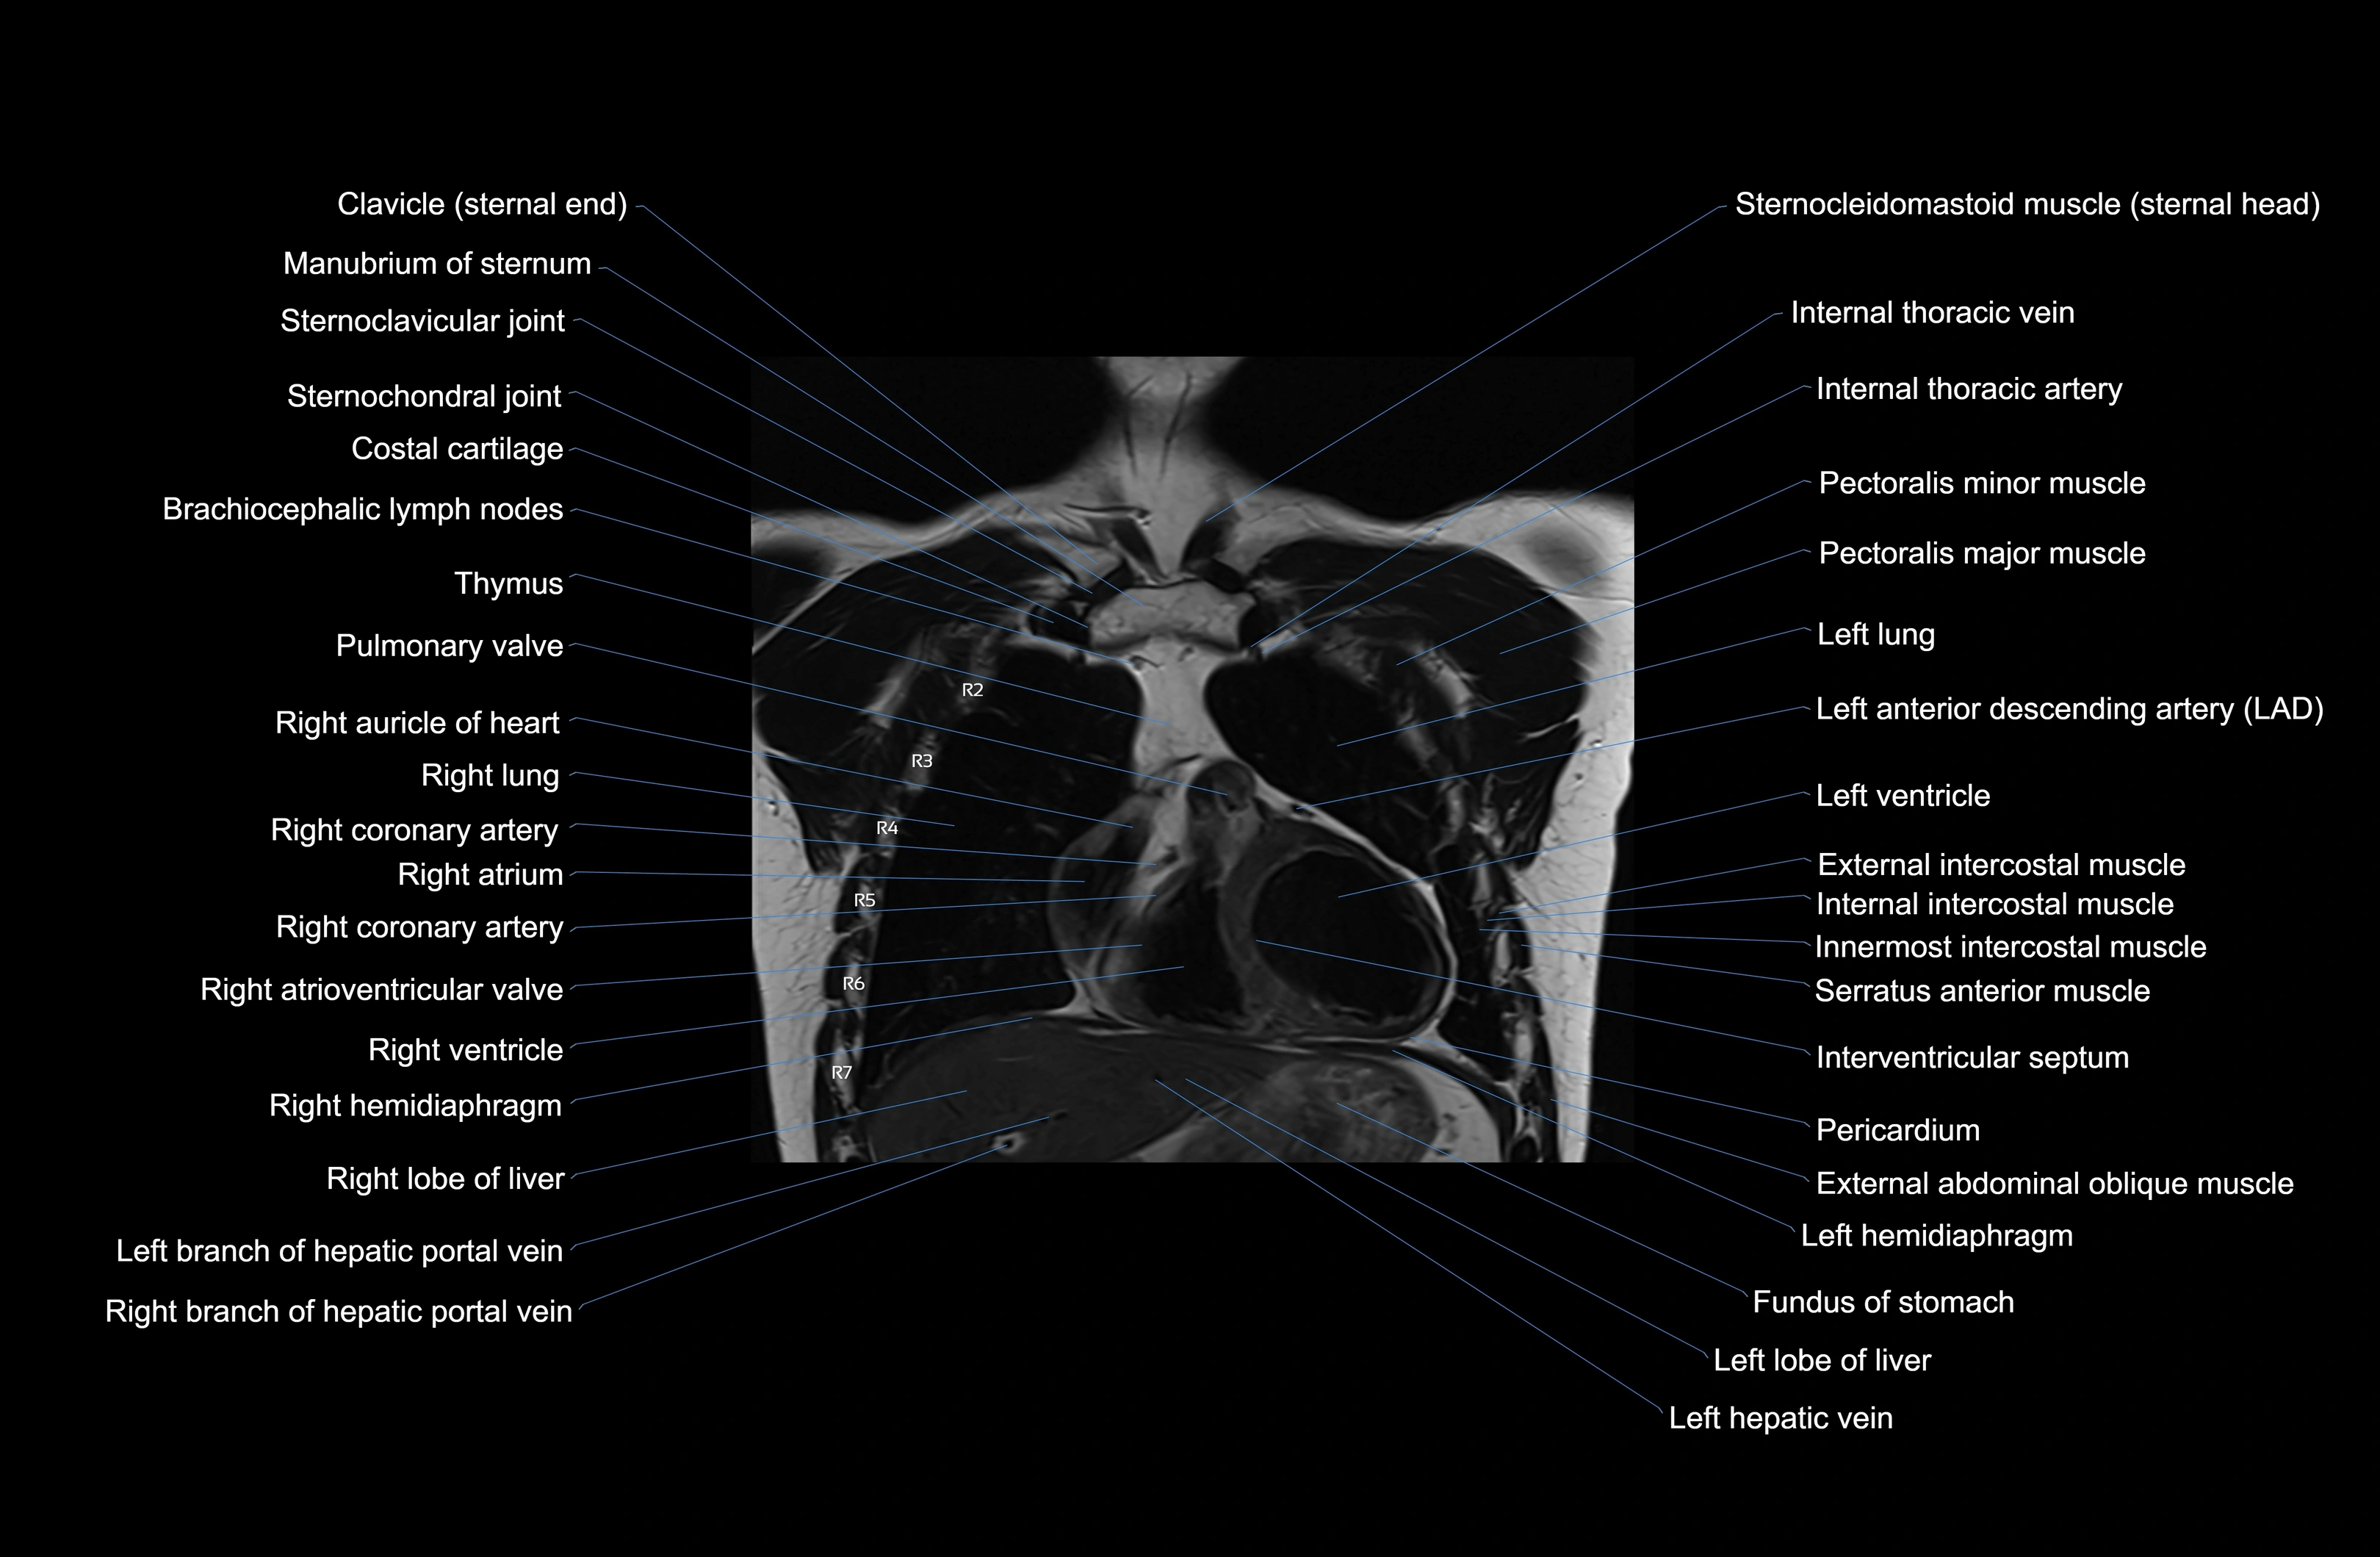

MRI images